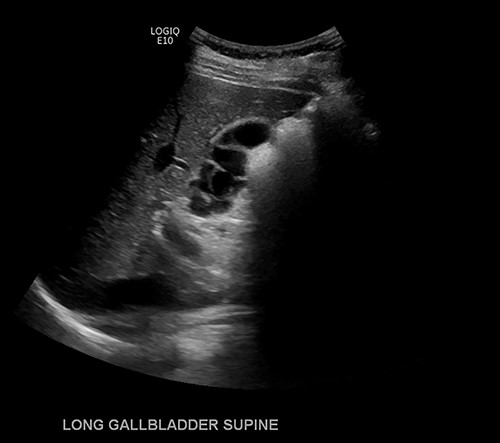

Given continued abdominal pain, RUQ ultrasound was performed revealing a multiseptated gallbladder (Fig. 1). She uneventfully underwent a laparoscopic cholecystectomy, which revealed multiple septations on gross inspection consistent with multiseptate gallbladder (Fig. 2). Pathologic evaluation demonstrated changes of chronic cholecystitis. She was asymptomatic on postoperative follow-up.

Ultrasound imaging of the gallbladder showing multiple septations resulting in a ‘sack of grapes’ appearance.